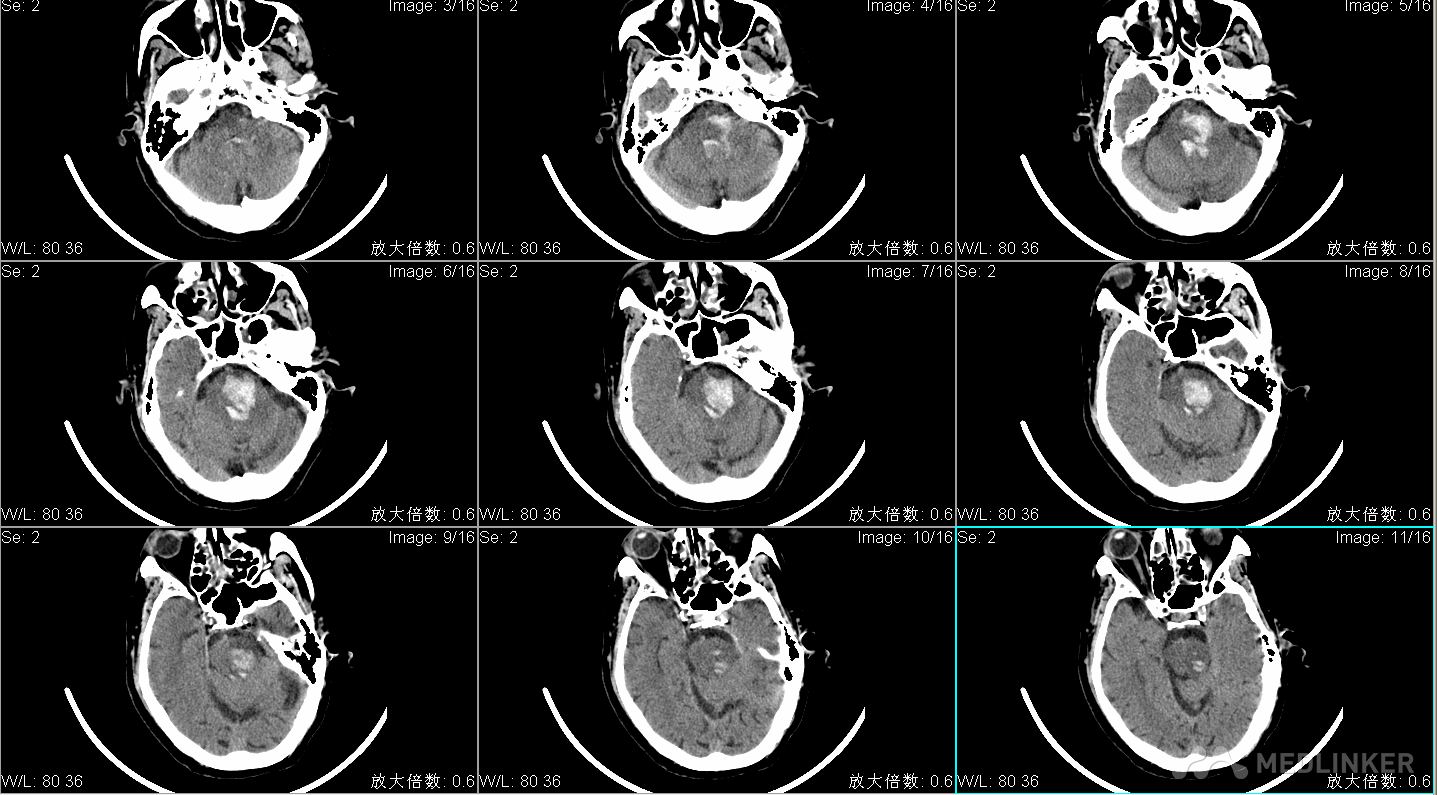

昏迷状态,刺痛不睁眼,无发声,四肢刺痛屈曲 ,GCS5分,双侧瞳孔直径左:右=1:1mm,光反射消失,眼球居中位,额纹对称,颈软,四肢刺痛屈曲,肌张力不高,腱反射(++),生理反射存在,双巴氏征(+)。 头CT显示脑干出血破入第四脑室,出血量约10ml。

术前头CT